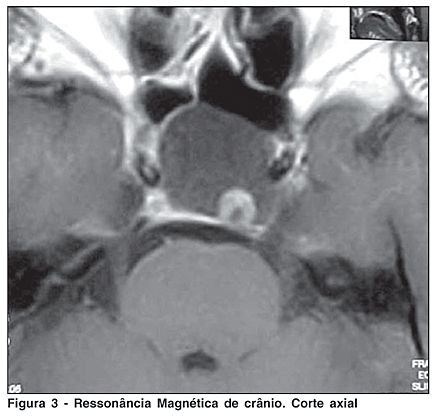

A ressonância magnética evidenciou lesão expansiva cística localizada na sela túrcica, com crescimento supra-selar, medindo cerca de 3,4 x 2,8 cm x 2,4 cm em seus maiores diâmetros, sem realce após o uso endovenoso de contraste. Apresentava obliteração da cisterna supra-selar e importante compressão sobre o quiasma óptico, sugestivo de macroadenoma predominantemente cístico (Figuras 2 e 3).